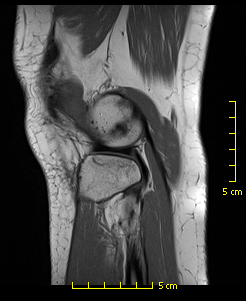

Additionally, I have avascular necrosis in both knees. I got the MRIs today, and it does not look good. I also have lupus, so AVN can be attributed to high dose (60mg) steroids for over a year, chemotherapy for over a year (to control the lupus), and the disease itself can also cause AVN (honestly it's most likely one of those things), but there are some weird looking patches on the bone that extend below the joint itself and there are black holes in parts of the bone (I don't really know what AVN looks like on an MRI so maybe that's all normal!).

Attached is an image with the weird holes from one of my MRIs...I have a ton of images, so I don't know which is the best to show what I'm talking about. It might just be AVN though!